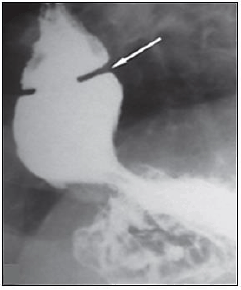

“Um paciente com diagnóstico de doença do refluxo gastroesofágico e queixa de disfagia realizou o seguinte exame contrastado do esôfago:”

Sobre o diagnóstico da imagem, assinale a afirmativa correta.

“Um paciente com diagnóstico de doença do refluxo gastroesofágico e queixa de disfagia realizou o seguinte exame contrastado do esôfago:”

Qual o diagnóstico mais provável?